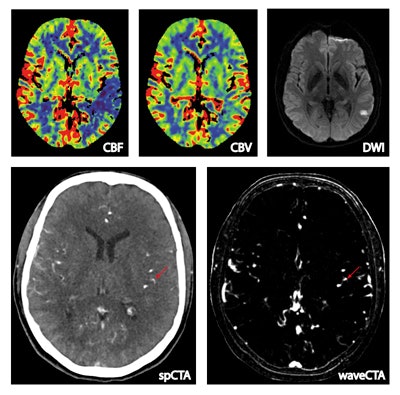

Above, a 55-year-old man presenting with right-sided hemiparesis and aphasia. Whole-brain CT perfusion (WB-CTP) shows a left-sided perfusion deficit in the middle cerebral artery territory with a mismatch between CBF und CBV. Follow-up MRI shows a relatively small final infarction volume. The wavelet-based CTA reconstructed from WB-CTP data demonstrates an M3 occlusion that is not evident in conventional CTA.Of these, 54.3% had a normal CT perfusion exam, and 45.7% (n = 287) had CT perfusion deficits. Among the 287 with perfusion deficits, 30% (n = 86) had a negative CTA exam, and among the 86 negative CTA patients, 73% had a confirmed stroke on follow-up CT or MRI within 72 hours. This left a final study population of 63 patients (mean age 74 years, range 34-89 years) with perfusion deficit, unremarkable CTA, but a confirmed stroke on follow-up.

The wavelet transform of CT perfusion data is based on time-signal profiles (signal refers to HU values) of each voxel. Voxels with bolus flow time-signal profiles (upper arrows) are enhanced, whereas unspecific profiles (lower arrows) are suppressed. Note the higher detail visibility and contrast-to-noise ratio of small vessels. All images courtesy of Dr. Wolfgang Kunz.